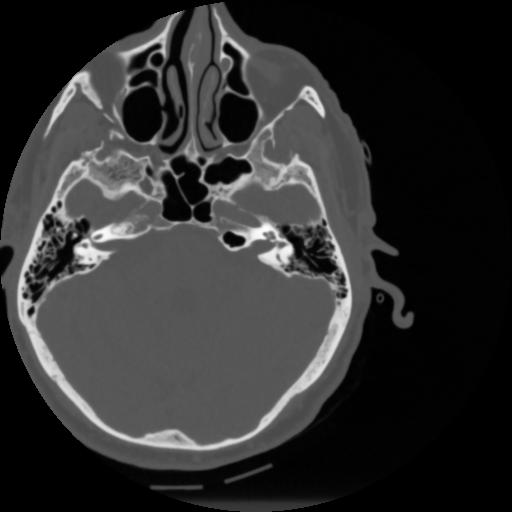

4 CEREBRO,,Vol,0.5,CEREBRO,,